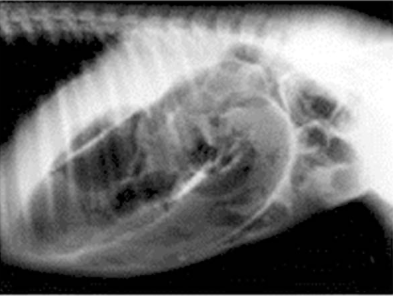

You are presented with an 18h colt foal at your clinic which had an uncomplicated birth and has been otherwise normal. It is now restless, off suck and constantly tail swishing/flagging. It has been straining. General physical exam parameters are within normal limits except for the abdomen is moderately distended with gas. No abnormalities are detected upon haematology or biochemisty. You decide to take a radiograph of the foal’s abdomen.

What is your diagnosis?

meconium impaction